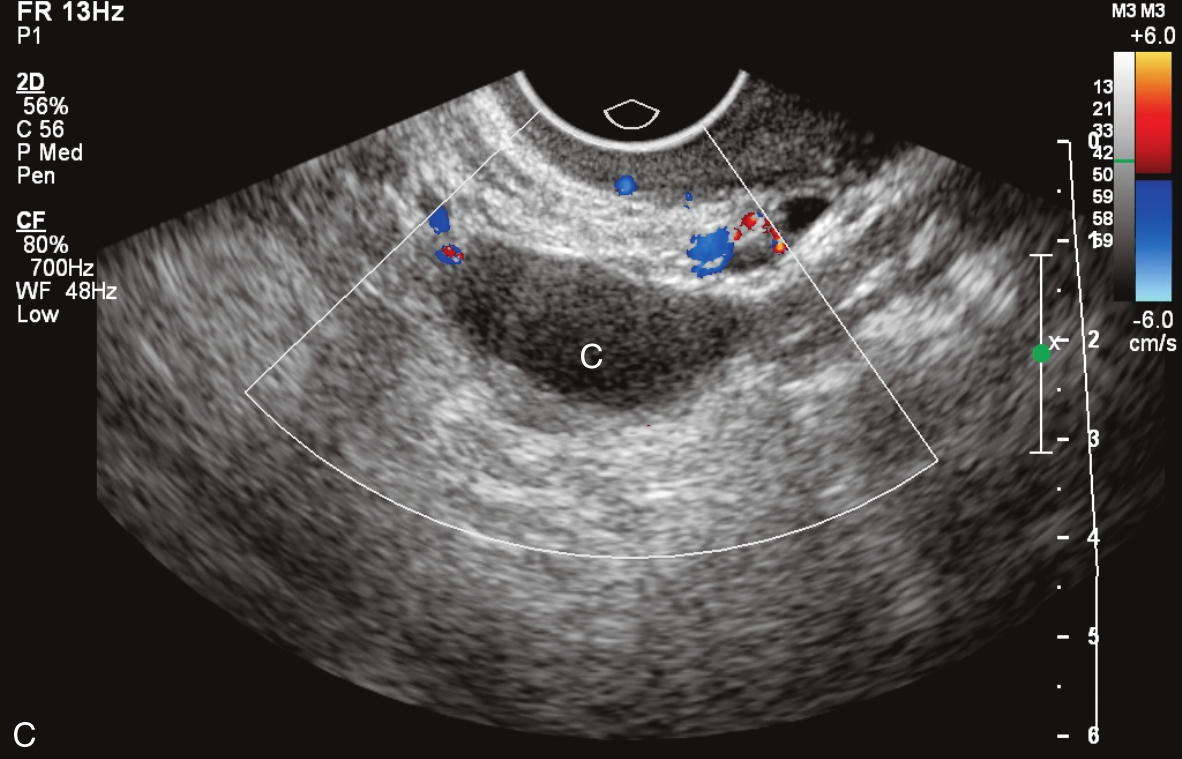

右卵巢上囊肿的经静脉超声造影见图3-12-4及ER 3-12-2。注入造影剂14s,囊肿囊壁开始出现增强(图3-12-4A箭头所示),晚于子宫肌层增强;注入造影剂后18s,囊壁呈较均匀等增强(图3-12-4B箭头所示);注入造影剂后22s,囊肿内始终未见造影剂进入(图3-12-4C箭头所示)。

图3-12-4 右卵巢上囊肿经静脉超声造影声像图

A.注入造影剂后14s;B.注入造影剂后18s;C.注入造影剂后22s。C:囊肿。

右卵巢上囊性占位病灶,经静脉超声造影有如下特点:①囊肿囊壁增强呈“慢进”;②囊壁呈较均匀等增强,其内始终未见造影剂进入。综上,造影表现为囊壁呈“慢进”的均匀等增强,囊内始终未见造影剂灌注;均提示囊肿良性可能。随访观察发现该囊肿自行消失。